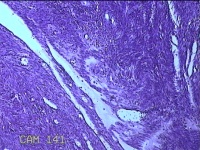

子宫肌瘤

性别

女

年龄

38岁

临床诊断

一般病史

发现子宫肌瘤复发7年余。

标本名称

大体所见

灰白粉红色结节样肿物8.5x5.5x4cm一个,表面糜烂,切面灰白色,编织状,质中。

富于细胞性平滑肌瘤

考虑富细胞平滑肌瘤。

组织处理和染色都不太理想。